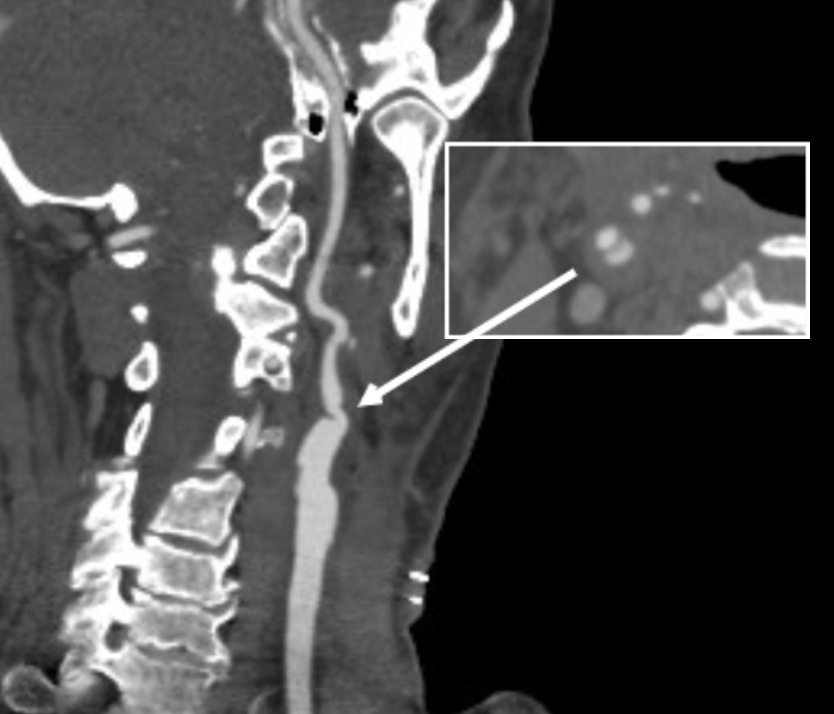

The patient is a man in his 80’s who presented with left sided weakness and dysarthria. Over 25 years before, he had undergone a carotid endarterectomy after a stroke, and had remained stroke free since. Per protocol, he received systemic thrombolysis and underwent CT angiography which revealed a right sided patch pseudoaneurysm.

Patch pseudoaneurysm with irregularities in lumenal wall of mural thrombus in right carotid bulb

This was seen dramatically on carotid duplex below.

Mural thrombus at carotid bifurcation compresses the right IJ vein